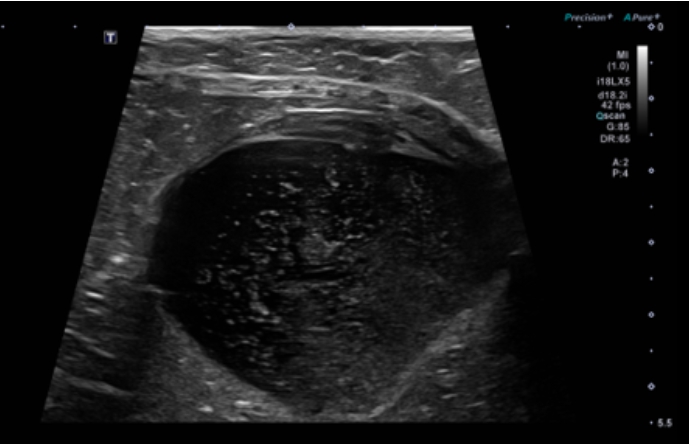

이어 진행한 복부 초음파에서는 방광 내 염증과 슬러지가 관찰되었으며, 결석이나 감염은 보이지 않아 특발성 방광염에 의한 FLUTD로 판단할 수 있었습니다.

또한 구토의 원인이 될 만한 위장관 이상도 따로 확인되지 않았습니다.▼